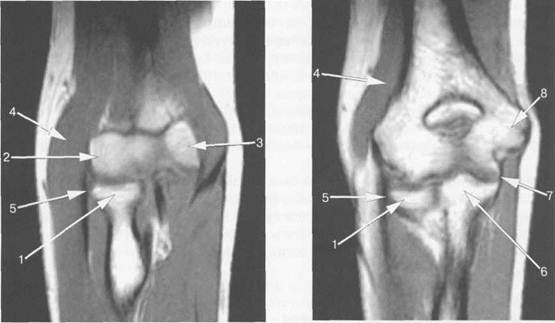

Рис. 19.34. MPT локтевого сустава. Корональная плоскость.

1 — головка лучевой кости; 2 — латеральный мыщелок плечевой кости; 3 — блок (медиальный мыщелок) плечевой кости; 4 — m. brachialis; 5 — сухожилие т. extensorisdigitorum; 6 — венечный отросток локтевой кости; 7 — ligamentum collateral ulnare; 8 — медиальный надмыщелок плечевой кости.